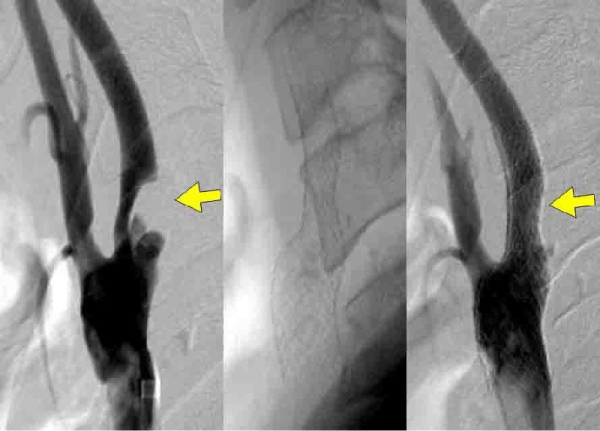

3. 脳血管内治療

脳梗塞の原因となる頸動脈狭窄症や、くも膜下出血の原因である脳動脈瘤に対しては、従来の脳神経外科的な手術(頸動脈内膜剥離術、脳動脈瘤クリッピング術)が行われてきましたが、より低侵襲で安全性や有効性が示されている脳血管内治療(頸動脈ステント留置術、脳動脈瘤コイル塞栓術)も可能になっています。

当院でも、脳血管内治療を積極的に行っておりますが、治療方針については、脳神経外科と連携し、患者さんとご家族にとって最適な治療が選択できるよう努めています。

その他、頭蓋内外の動脈の血管形成術や頭頸部の腫瘍に対する塞栓術など、幅広い脳血管内治療を行っています。